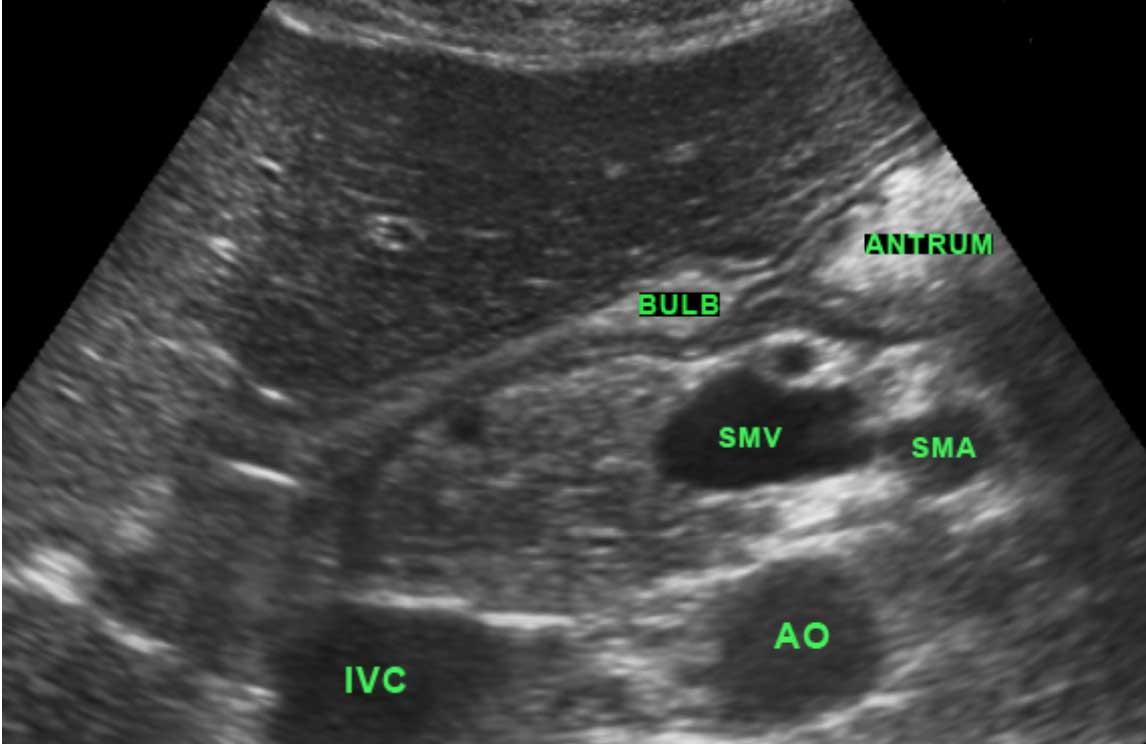

Hang vị và hành tá tràng là những phần của dạ dày được xác định rõ nhất bằng siêu âm.

Môn vị được nhận biết là sự dày lên cục bộ của lớp cơ ở phía xa so với hang vị.

Thành của hành tá tràng mỏng hơn thành dạ dày.

Dịch vị có thể được sử dụng để cải thiện khả năng quan sát vùng hang vị và tá tràng, bằng cách cho bệnh nhân nằm nghiêng sang phải: khí nổi lên vùng đáy vị, và dịch chảy vào hang vị và hành tá tràng.

Điều này đặc biệt hữu ích ở người lớn mắc bệnh loét dạ dày tá tràng.